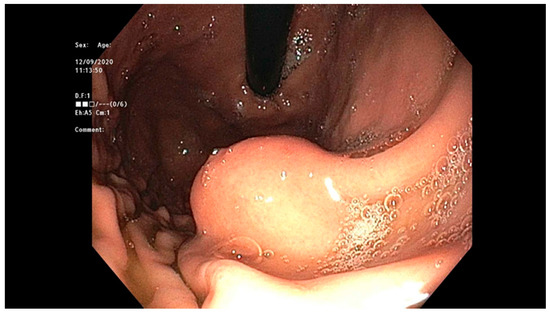

4.4. Gastrointestinal Stromal Tumor (GIST)

- Rubin, B.P.; Heinrich, M.C.; Corless, C.L. Gastrointestinal stromal tumour. Lancet 2007, 369, 1731–1741. [Google Scholar] [CrossRef]

- Cai, J.-Q.; Yu-Cheng, Z.; Mou, Y.-P.; Pan, Y.; Xu, X.; Zhou, Y.-C.; Huang, C.-J. Laparoscopic versus open wedge resection for gastrointestinal stromal tumors of the stomach: A single-center 8-year retrospective cohort study of 156 patients with long-term follow-up. BMC Surg. 2015, 15, 1–10. [Google Scholar] [CrossRef] [PubMed]

- Kim, H.H.; Uedo, N. Hybrid NOTES. Gastrointest. Endosc. Clin. North Am. 2016, 26, 335–373. [Google Scholar] [CrossRef] [PubMed]